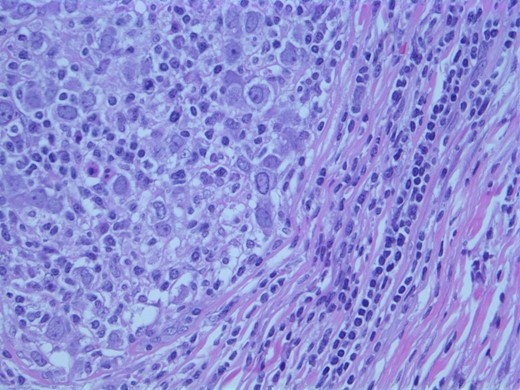

The findings were discussed with the patient and she subsequently underwent a modified radical mastectomy. Pathology of the specimens showed poorly differentiated apocrine carcinoma with extensive axillary node metastases (Fig. 4). The invasive carcinoma measured 1.5 × 1.4 × 1.3 cm without invasion into the skin or muscle. The margins were uninvolved.